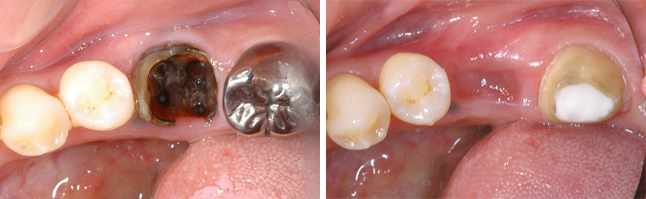

過去に抜いてインプラントにした方が良いと言われ 心配で当院を受診された35歳男性

BEFORE

向かって左端で横を向いてはえているのが親知らずを、抜歯せざるを得ない状態の放置された虫歯に移植します。

AFTER

治療後5年のレントゲンとそのカラー写真です。 この方の反対側の顎の中に埋もれている親知らずを抜歯し、即時移植で治療することができました。